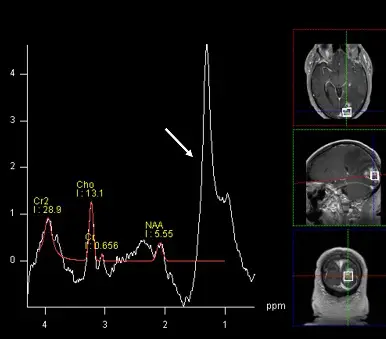

如下圖,在放射性腦壞死的 MR spectroscopy ( MRS )頻譜上, 1 ~ 1.5 ppm 的地方有相當寬的頻峰,通常是指下列何種代謝物?

- 影像類型:單體素質子磁振頻譜(Single-voxel 1H-MRS)與輔助定位的 MRI 影像(軸切、矢狀、冠狀 T1 顯影後影像)。

- 定位影像:顯示腦部有一明顯對比劑強化的病灶,且游標(voxel)正放置於該病灶上擷取訊號。

- 頻譜特徵:

- NAA (N-acetylaspartate):約落在 2.0 ppm,波峰明顯下降,代表正常神經元破壞。

- Cr (Creatine):約落在 3.0 ppm(及 3.9 ppm 的 Cr2)。

- Cho (Choline):約落在 3.2 ppm。

- 白色箭頭所指波峰:在 1.0~1.5 ppm 之間出現一個非常寬大且高聳的波峰(約以 1.3 ppm 為中心)。在放射性腦壞死的病理環境下,這個寬峰是大量游離脂質(Lipid)與乳酸(Lactate)的重疊